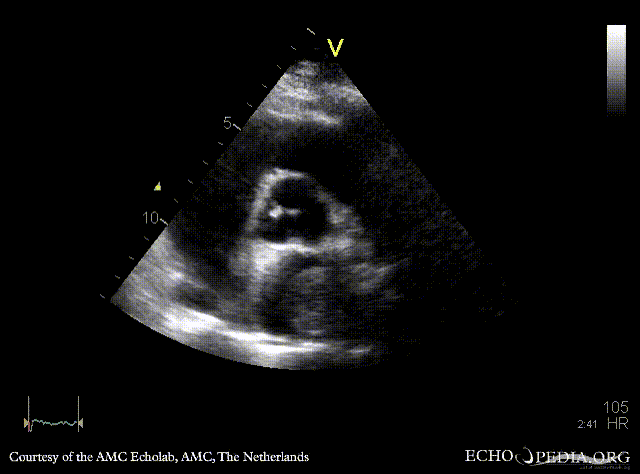

| Courtesy of: AMC Echolab, AMC, The Netherlands | |

| PSAX: tumor mass in left atrium | A4CH |